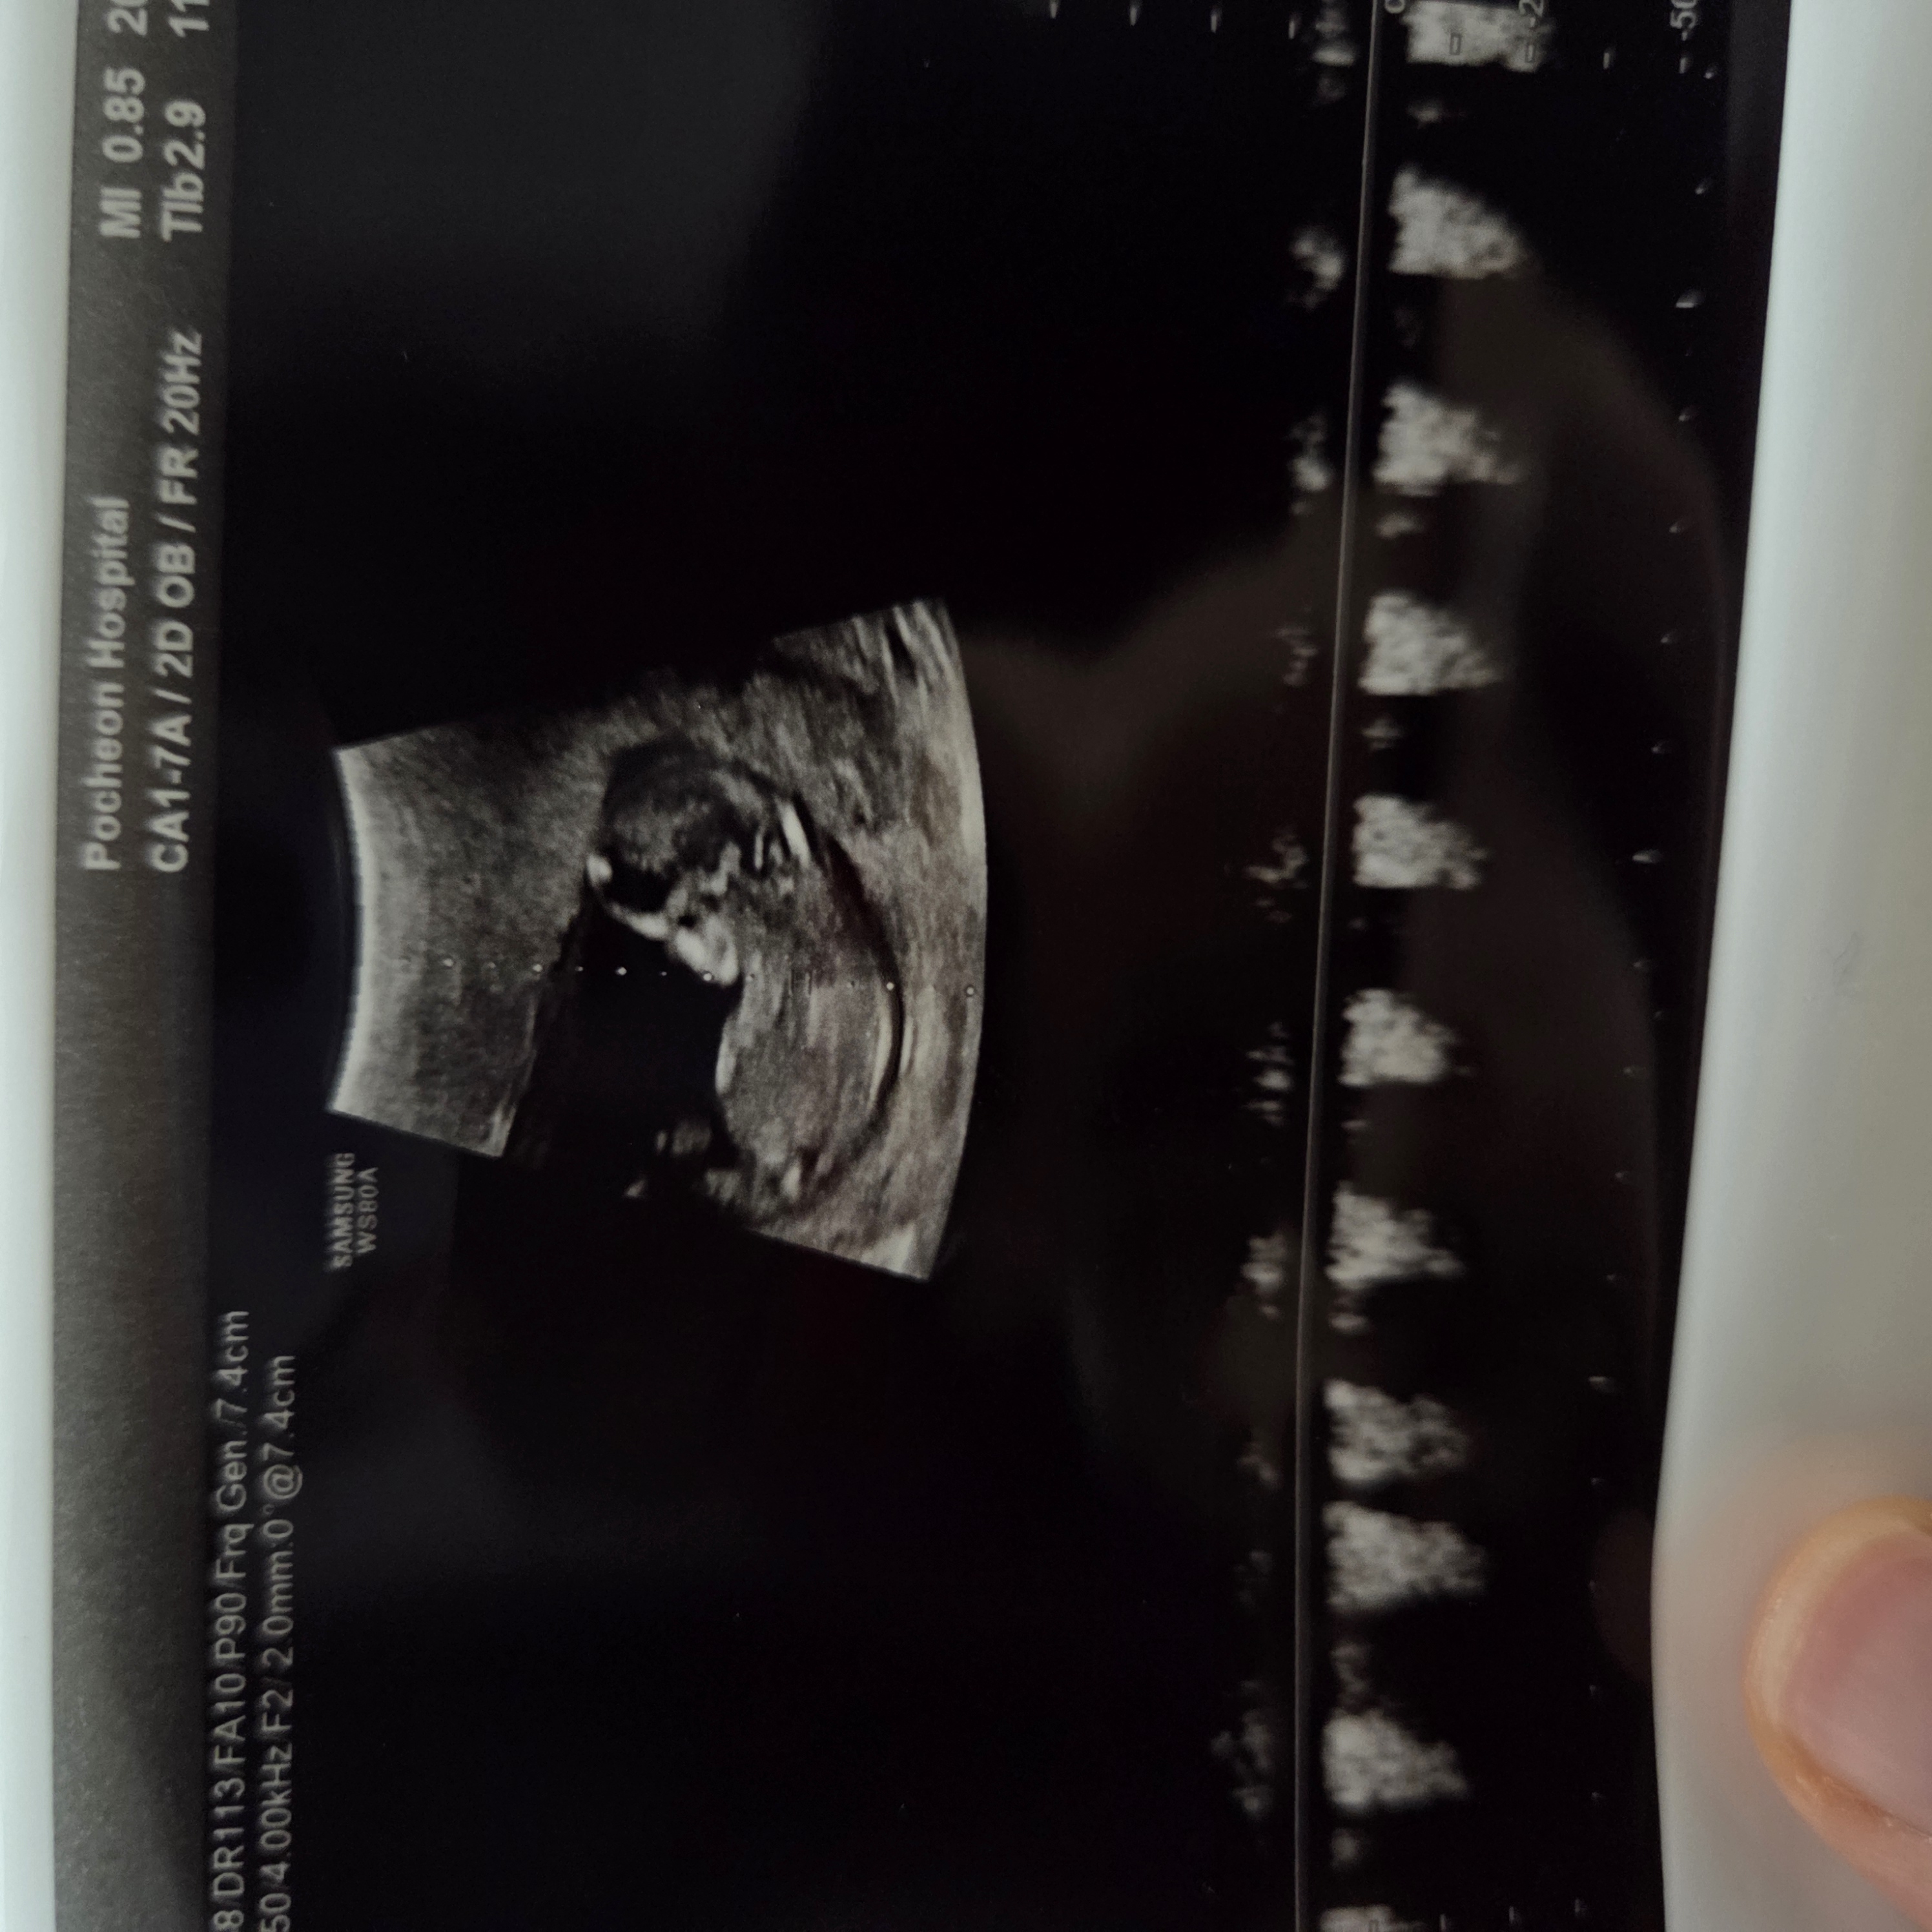

아들일까요~ 딸일까요?! 의사쌤은 다리사이에 뭔가 보이는거 같다고 아들일거같다곤 하셨는데 남편이 너무 절망하고 있어서욬ㅋㅋㅋㅋㅠㅠ 선배맘들은 어떻게 보이시나요?!

아들같아유

찍힌게 다리같아보이기도해서 애매하네요 ㅎㅎ 저희남편도 처음 아들확정이었을때 적막흐르면서 아쉬운티를 못숨겼는데ㅋㅋㅋㅋ 막상 태어나니까 매일 뽀뽀하고 너무너무 예뻐하더라구요ㅋㅋ아들이던 딸이던 예쁠거에요❤️